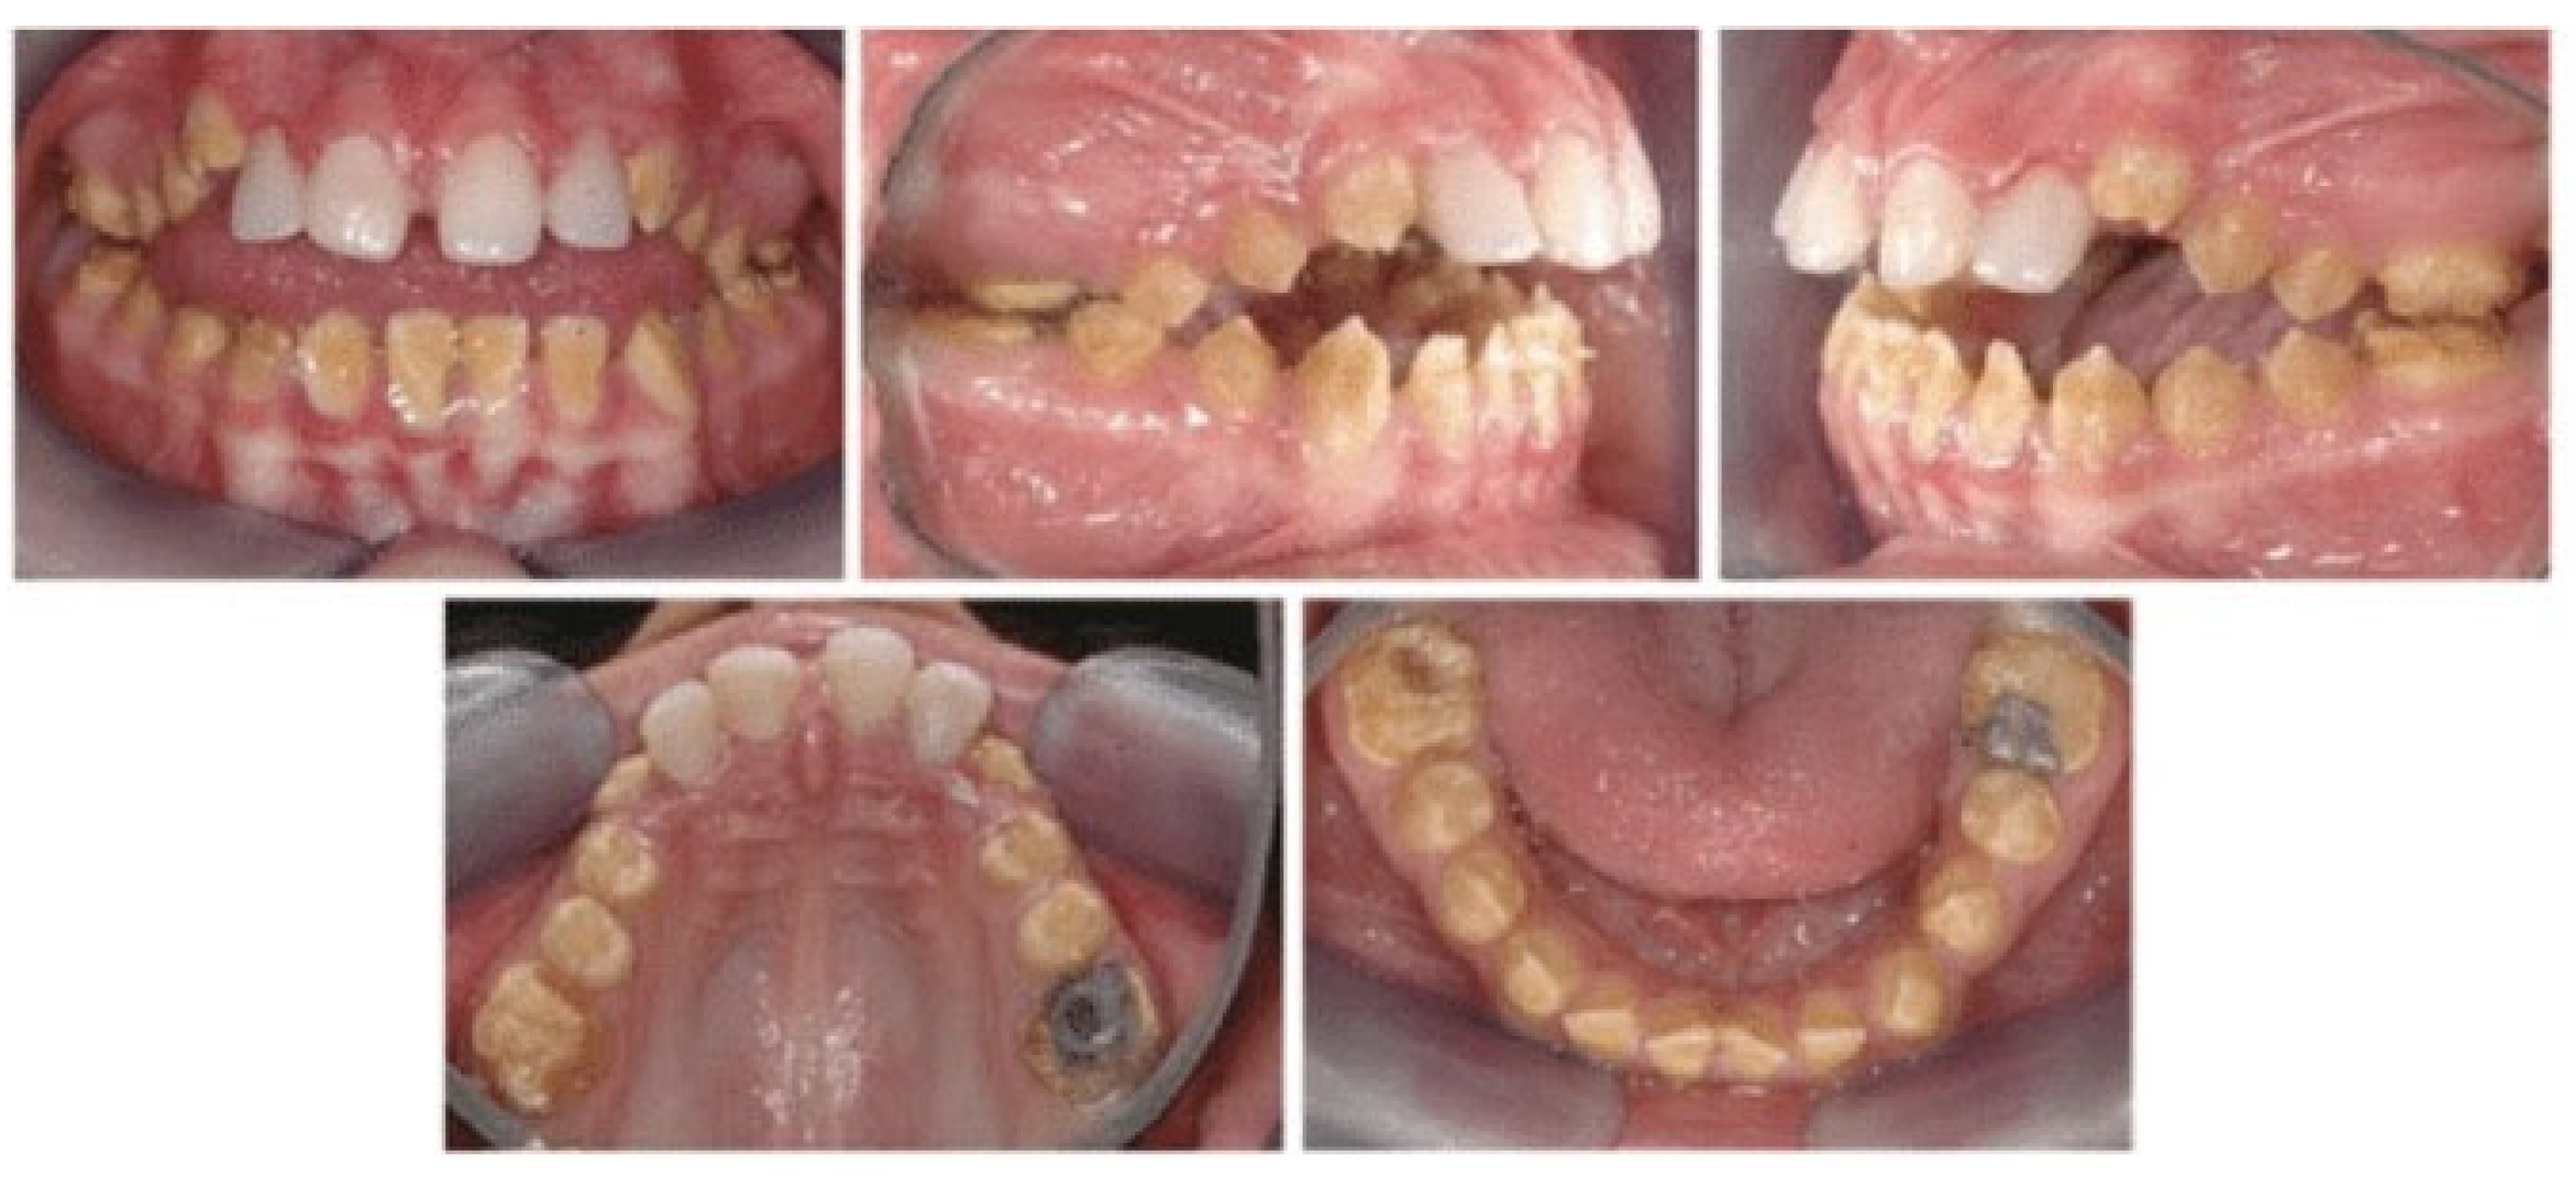

1.1. Amelogenesis Imperfecta (AI) and Its Consequences

- Class 3 (in blue): Description of Dental Symptoms (29.1%), with the following top words: “dent”, “molaire”, “couronne”, “lait”, “toucher”, “poser”, “incisive”, “fils”, “carie”, “abîmer”, “jaune”. This is the most concrete and symptom-centered class, focusing on dental manifestations and terminology. It includes references to deciduous teeth (“lait”), materials (“résine”), stages (“sortie”), and treatments (“couronne”). This suggests parents or individuals are detailing clinical signs and treatment attempts. we propose to label this class “Dental symptoms and treatment experiences”;